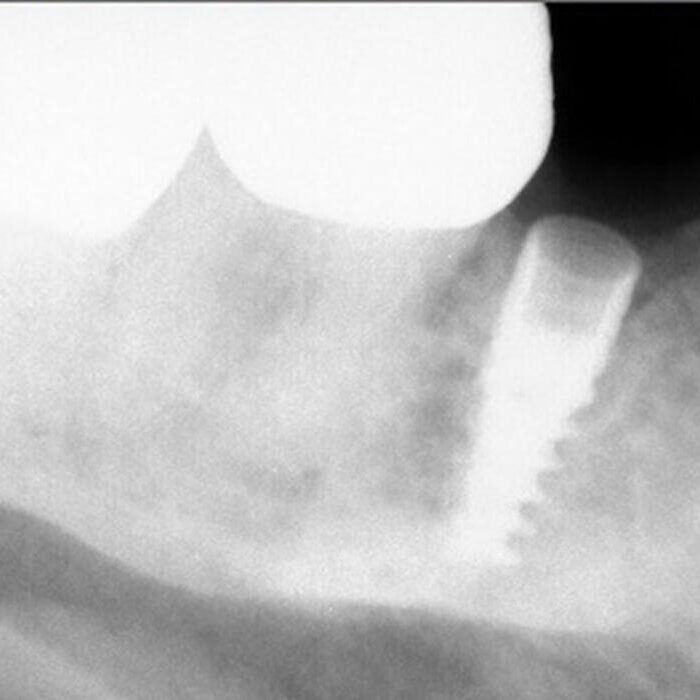

ULTRASONICS: Complications of Abutment Screw Retrieval Secondary to Prior Ultrasonic Attempts

There has been much written on the use of ultrasonics in retrieving fractured screw fragments, which I didn’t think a lot about until May of 2023, as it has not been a part of my fractured screw retrieval algorithm.